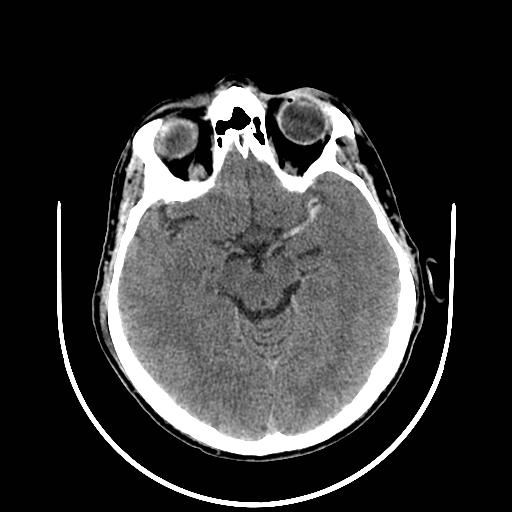

岛叶带征(岛带征)

正常情况下,岛叶皮层的灰质与白质界限清晰。当岛叶皮层发生急性脑梗死时,CT 图像上会出现带状低密度影,这便是所谓的岛叶带征。